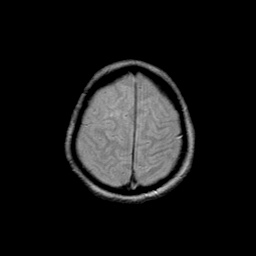

Basal Ganglia Calcification: proton density-weighted MR -- Slice #15

[Home][Help][Clinical] Slice 15